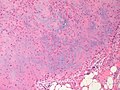

Chondromyxoid fibroma. H&E stain. | |

| LM | spindle cells or stellate cells in a myxoid or chondroid stroma, lobules with hypocellular centers and hypercellular peripheries, +/-giant cells in the hypercellular periphery, scattered calcifications, no true hyaline cartilage formation, no mitotic activity |

- Spindle cells or stellate cells in a myxoid or chondroid stroma.

- Lobules with hypocellular centers and hypercellular peripheries.

- Giant cells in the hypercellular periphery.

- Scattered calcifications.

- No true hyaline cartilage formation.

- No mitotic activity.